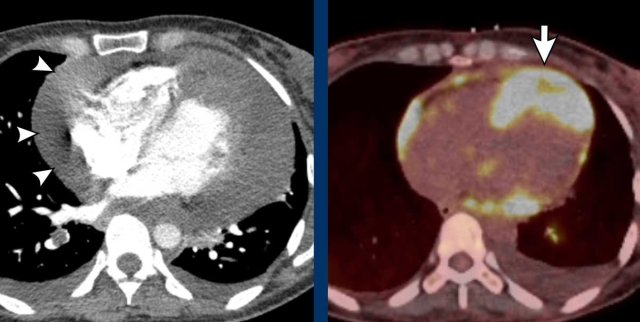

Image

Perfusion defect in LAD territory of 45 year old trauma patient, who presented after a fall from the stairs during heavy lifting.

A sharper window setting helps to assess the myocardial attenuation differences.